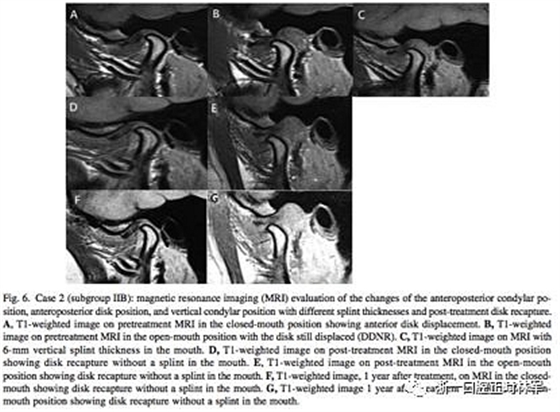

在治療12個月后,IIB組中有7例關(guān)節(jié)盤完全復(fù)位,而IIA組0例。在這7例中,張閉口位關(guān)節(jié)盤均復(fù)位的只有3例,其余4例只有在張口位時復(fù)位了(即從DDNR轉(zhuǎn)變?yōu)镈DR,分別見圖5和圖6)。再過一年后,對這7例進(jìn)行MRI研究,發(fā)現(xiàn)關(guān)節(jié)盤保持于其復(fù)位的位置。